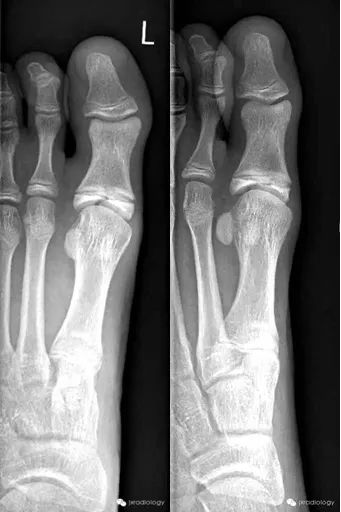

骨骺裂必须和骨折鉴别。一般骨折损伤2-3周后复查平片可见愈合的迹象。识别这个现象是重要的,以避免过度治疗和不必要的手术干预。

A cleft epiphysis has to be differentiated from fracture. Generally fractures demonstrate signs of healing if the radiograph is repeated 2-3 weeks after injury. Recognition of this entity is important to avoid over treatment and unnecessary surgical intervention.

Cleft epiphysis意译为骨骺裂,结合临床病史及复查才能和骨折区分。

黄箭骨折;蓝箭是骨骺裂。LEFT a subtle lateral condyle fracture. Less than 2 mm displacement and probably stable. RIGHT a different case. Oblique view gives nice impression of fracture. Blue arrow indicates a cleft epiphysis of the radius (normal variant)